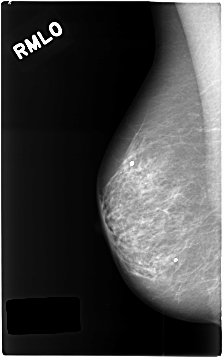

C_0453_1.RIGHT_MLO

DATE_OF_STUDY 16 10 1995

PATIENT_AGE 63

DENSITY 2

RIGHT_MLO LINES 4632 PIXELS_PER_LINE 2904 BITS_PER_PIXEL 12 RESOLUTION 50 NON_OVERLAY

LESION_TYPE MASS SHAPE OVAL MARGINS ILL_DEFINED

ASSESSMENT 4

SUBTLETY 5

PATHOLOGY BENIGN_WITHOUT_CALLBACK

LESION_TYPE MASS SHAPE OVAL MARGINS SPICULATED

SUBTLETY 4